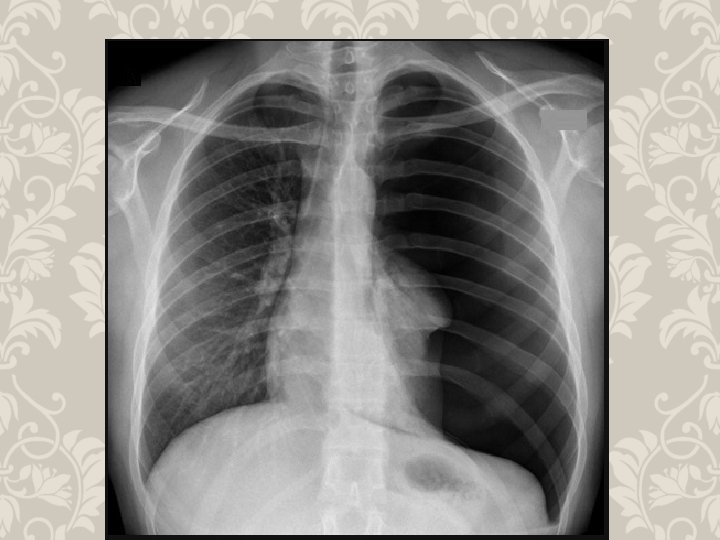

HEMOTHORAX life-threatening injury number one A massive hemothorax is defined as >1500 m. L of blood or, in the pediatric population, one third of the patient's blood volume in the pleural space tube thoracostomy is the only reliable means to quantify the amount of hemothorax After blunt trauma, a hemothorax usually is due to multiple rib fractures occasionally bleeding is from lacerated lung parenchyma a massive hemothorax is an indication for operative intervention Indication of emergency toracotomy

HEMOTHORAX PHYSICAL FINDINGS

RIB FRACTURE WITH HEMOTHORAX